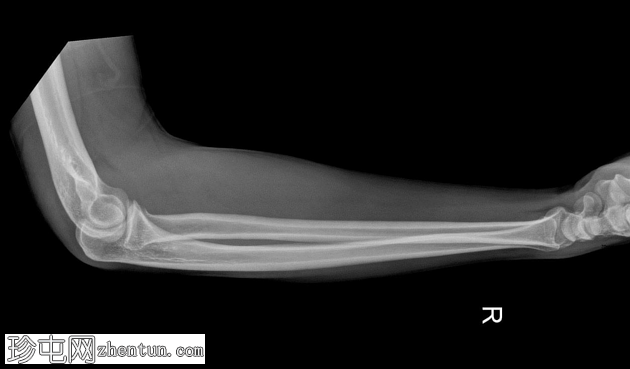

4.png

侧位片

桡骨头关节内粉碎性骨折,关节面轻微凹陷。肱骨远端前侧可见移位的骨碎片,桡骨头位片上清晰可见。可见前后脂肪垫征,提示肘关节积液。

未见肘关节脱位,肱桡骨小头排列保持正常。冠突水平可见复合阴影,可能与软组织重叠或投影伪影有关。桡骨和尺骨骨干外观完整,无骨折征。周围软组织肿胀。

本例患者前后脂肪垫征均存在,证实存在关节内积液,符合急性关节内损伤的诊断。未见肘关节脱位或相关骨干骨折,提示损伤仅限于桡骨头。

根据影像学特征,该骨折符合 Mason III 型损伤,涉及多个骨折碎片和关节面破坏。此类骨折需要骨科评估,并根据其稳定性和移位情况,选择手术治疗或桡骨头置换术。